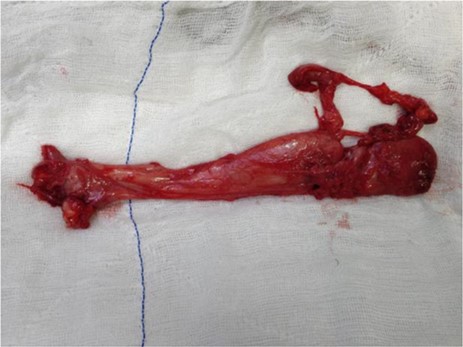

The mass was removed by wide local excision through a pararectal incision maintaining a plane between the rectum and the swelling. The cavity was closed in layers with placement of a corrugated drain (Figs 2 and 3). Final histopathological report was suggestive of a spindle cell tumour and subsequent immunohistochemistry revealed an AAM.